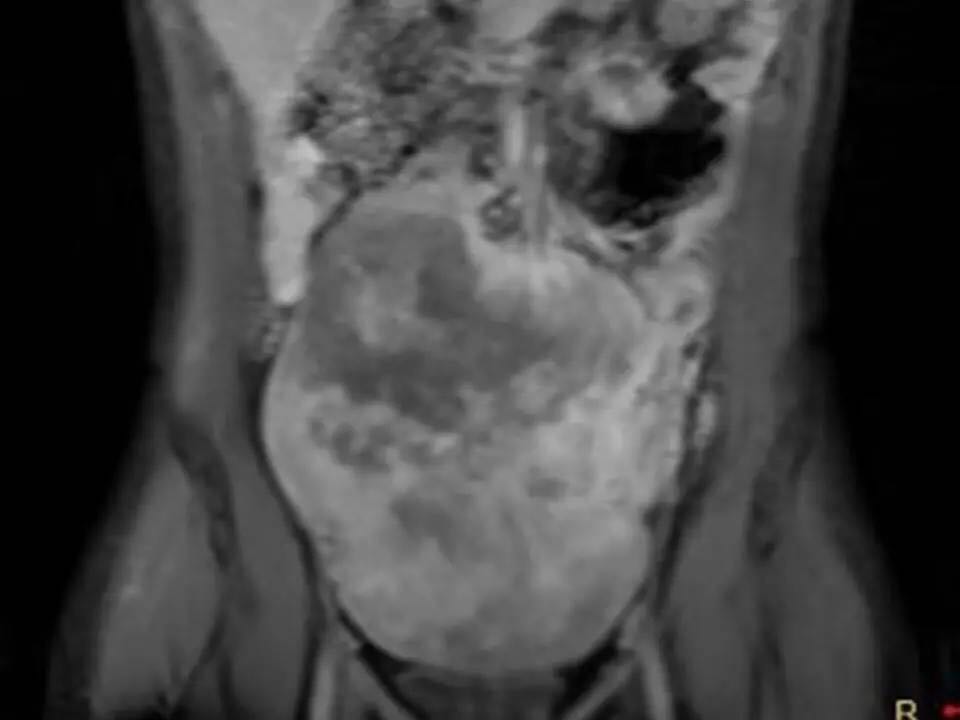

MRI表现,腹盆腔见不均质肿块,与肌肉相比为等低密度,强化不明显。T1WI信号均匀,T2WI高低混杂信号,增强后渐进性强化,病变各序列可见斑片状低信号区。 诊断,腹腔侵袭性纤维瘤病。

AF的影像学表现具有一定特征性。影像上表现为边界欠清的软组织肿块,钙化、出血少见,即便在较大的肿瘤中也看不到中央性坏死。病灶CT密度欠均匀,与邻近骨骼肌相近,强化不明显。T1WI信号基本均匀,明显或中度强化,典型强化方式呈渐进性。所有序列中都可以看到一定的低信号区,在病理上相对应的为病变内胶原纤维丰富的区域,此区域强化较轻。 侵袭性纤维瘤病虽然少见,但是平常工作中需要考虑到侵袭性纤维瘤病的诊断,尤其是中年女性腹腔的肿块。MRI为最佳的检查方法,可以显示一定的影像学特征。